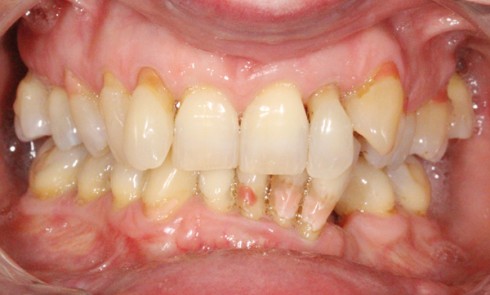

Les MIH se manifestent par des taches jaune brun ou blanchâtres préférentiellement localisées sur la moitié occlusale coronaire si l’intégralité...